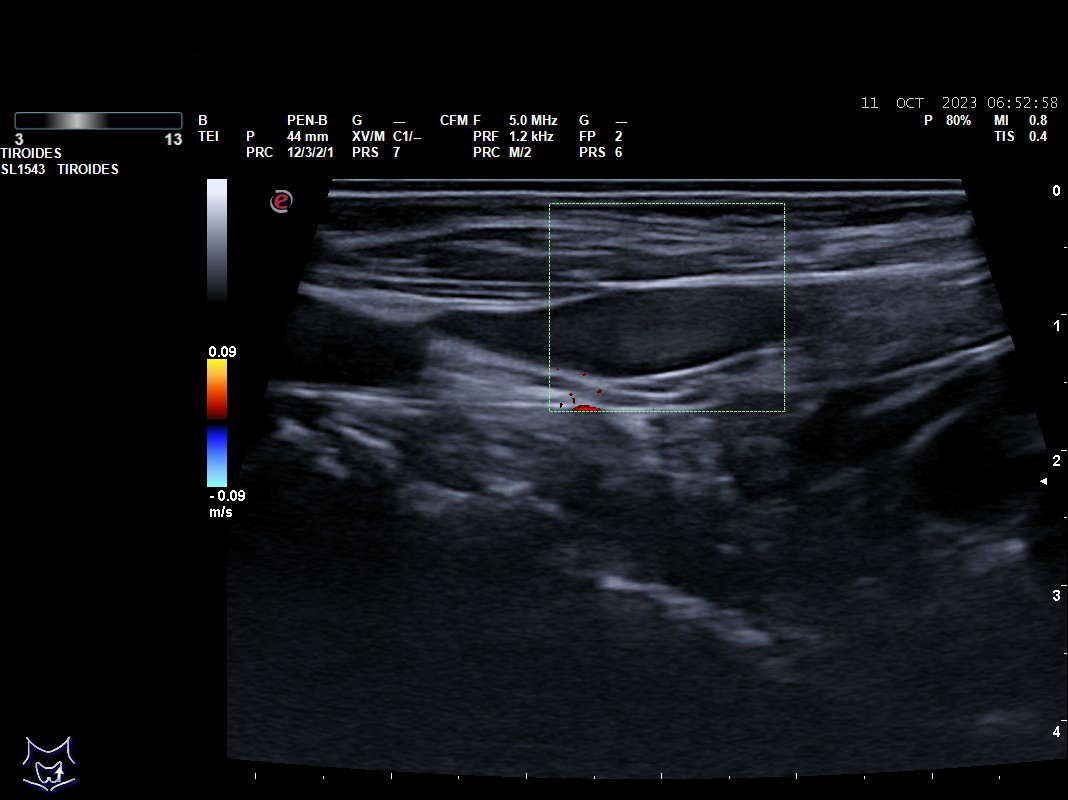

Hallazgos ecográficos: nódulos tiroideos subcentimétricos sin cambios, yugular interna izda con contenido discretamente hiperecogénico que no capta Doppler y colapsabilidad incompleta.

El diagnóstico se realiza con eco-doppler y TAC.